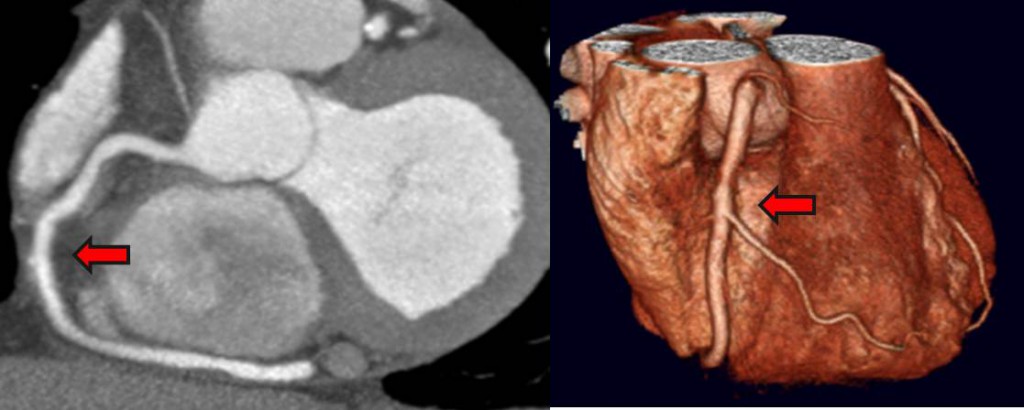

در این روش از کامپیوتر برای آنالیز و در کنار هم قرار دادن تصاویر سی تی اسکن استفاده می شود. به این صورت که گامپیوترهای قوی سی تی آنژیو می توانند از کنار هم قرار دادن مجازی تصاویر کنار هم یک تصویر طولی و حتی سه بعدی ایجاد نمایند و به این روش می توان طول رگ را مشاهده کرد و بیماریهای مختلف آن را تشخیص داد.

سی تی آنژیوگرافی در اصل بازسازی کامپیوتری تصاویر بدست آمده از سی تی اسکن عادی است و این بازسازی می تواند در پلن ها و در برش های مختلف تصویر خیلی خوب و قابل تفسیر از عروق و اعضای بدن ایجاد نماید.